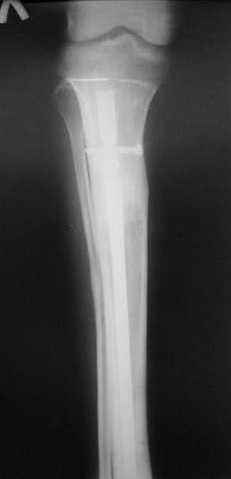

Реализовал описанную выше методику, и в итоге вот что получилось. Высылаю лишь прямые проекции,

в боковых тоже всё в тему.

Сейчас аппарат сняли, но случай ещё не завершенный.

Признаюсь честно, не совсем уверен в прочности консолидации на стыке косточек. Кроме того, укорочение в районе 6 см. Сейчас реабилитация - ходит опираясь на ногу с одним костылем.

Продолжение, видимо, будет... Возможно, будем удлинять.